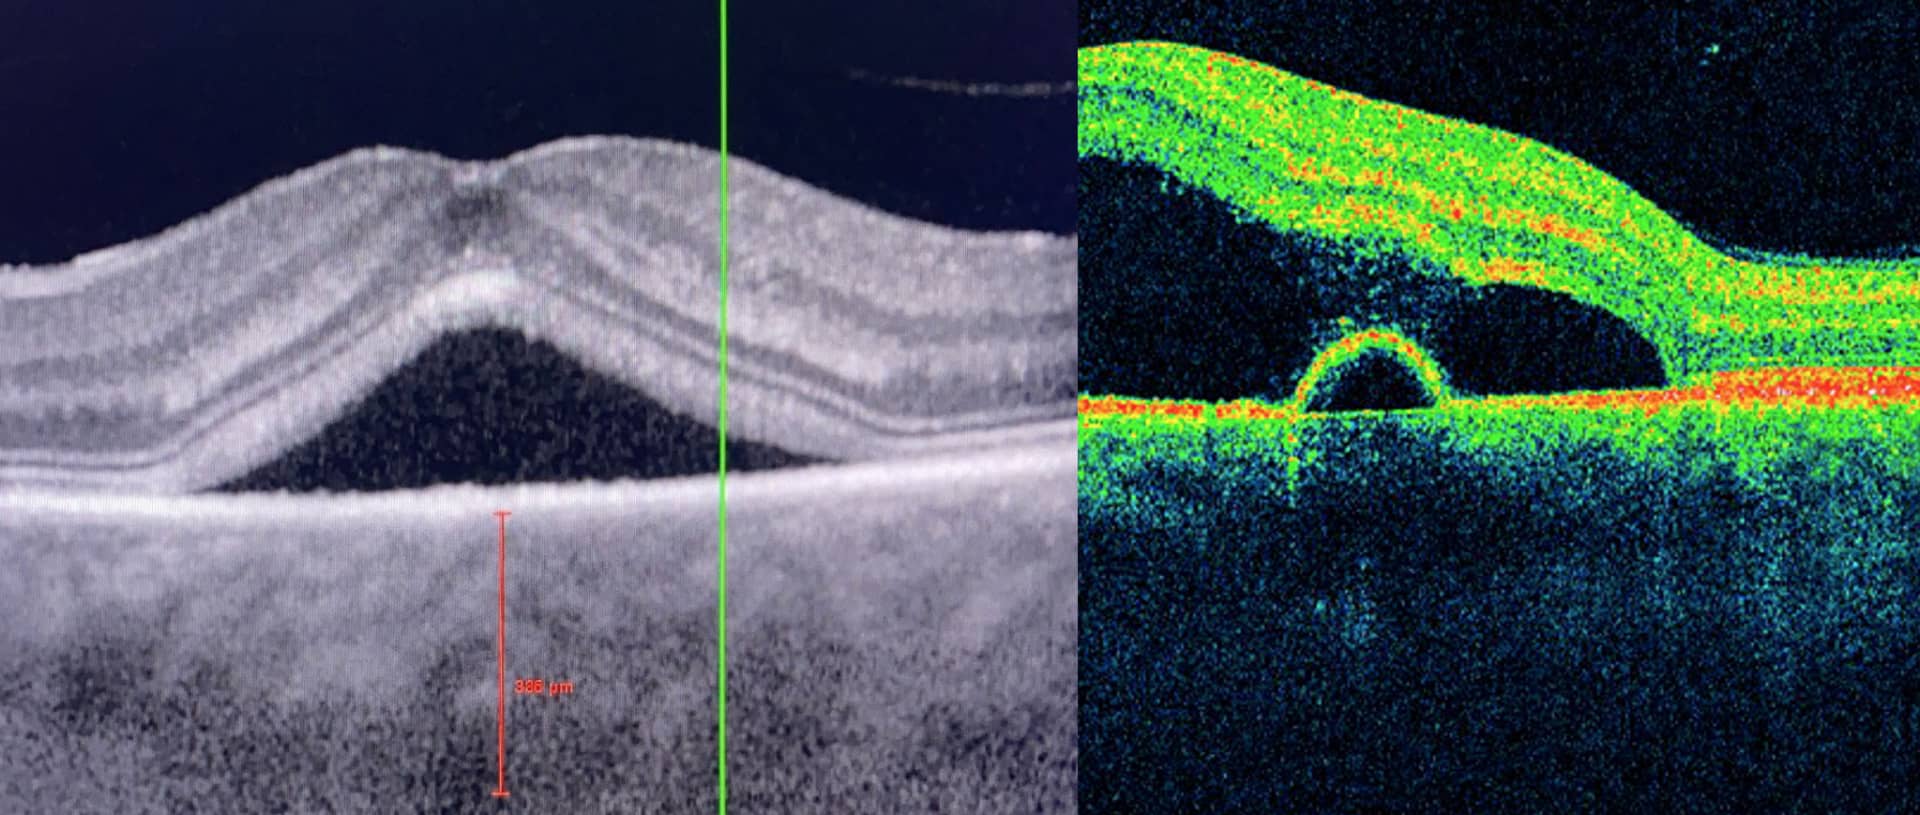

Le trou maculaire est une dégénérescence rétinienne fovéolaire, uni ou bilatérale, résultant principalement d’une traction vitréo-maculaire importante.

Les facteurs de risque comprennent l’âge > 65 ans et le sexe féminin.

La réalisation d’OCT maculaire est l’examen de référence pour diagnostiquer un trou maculaire. Il permet également d’éliminer les diagnostics différentiels.